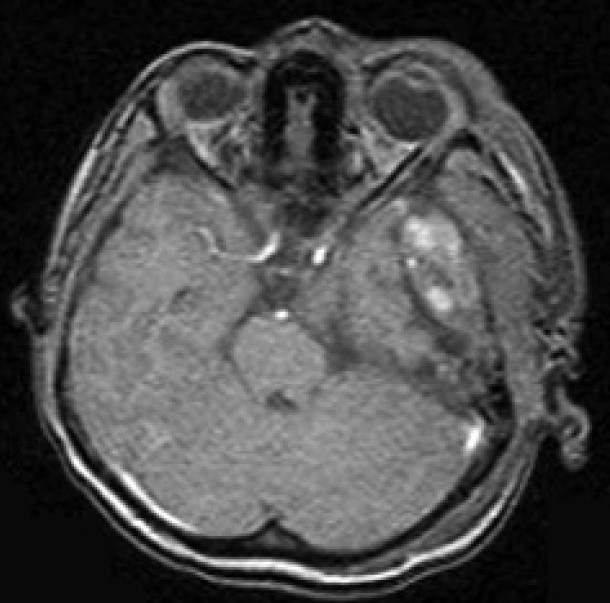

The Computed Tomography Scan (CT Scan) of the brain showed a rounded, well-defined, heterogeneously hyperdense, enhancing lesion in the left temporoparietal region, with a mass effect and destruction of the left temporal bone, extending into the scalp, suggesting the possibility of a meningioma. No evidence of calcification was noted within the lesion [Figure 1]. Magnetic resonance imaging (MRI) of the brain showed a left temporal lesion, hypointense on T1, heterointense on T2, with heterogeneous enhancement [Figure 2]. The lesion measured 6.0×4.6×7.4 cm. A significant mass effect was detected with a midline shift to the right, of 15 mm. The diffusion weighted image showed mild restriction. Magnetic resonance spectroscopy showed choline and N-Acetyl Acetate peaks.

| Fig. 2 Preoperative MRI of the brain showed a left temporal lesion, hypointense on T1, heterointense on T2, with heterogenous enhancement